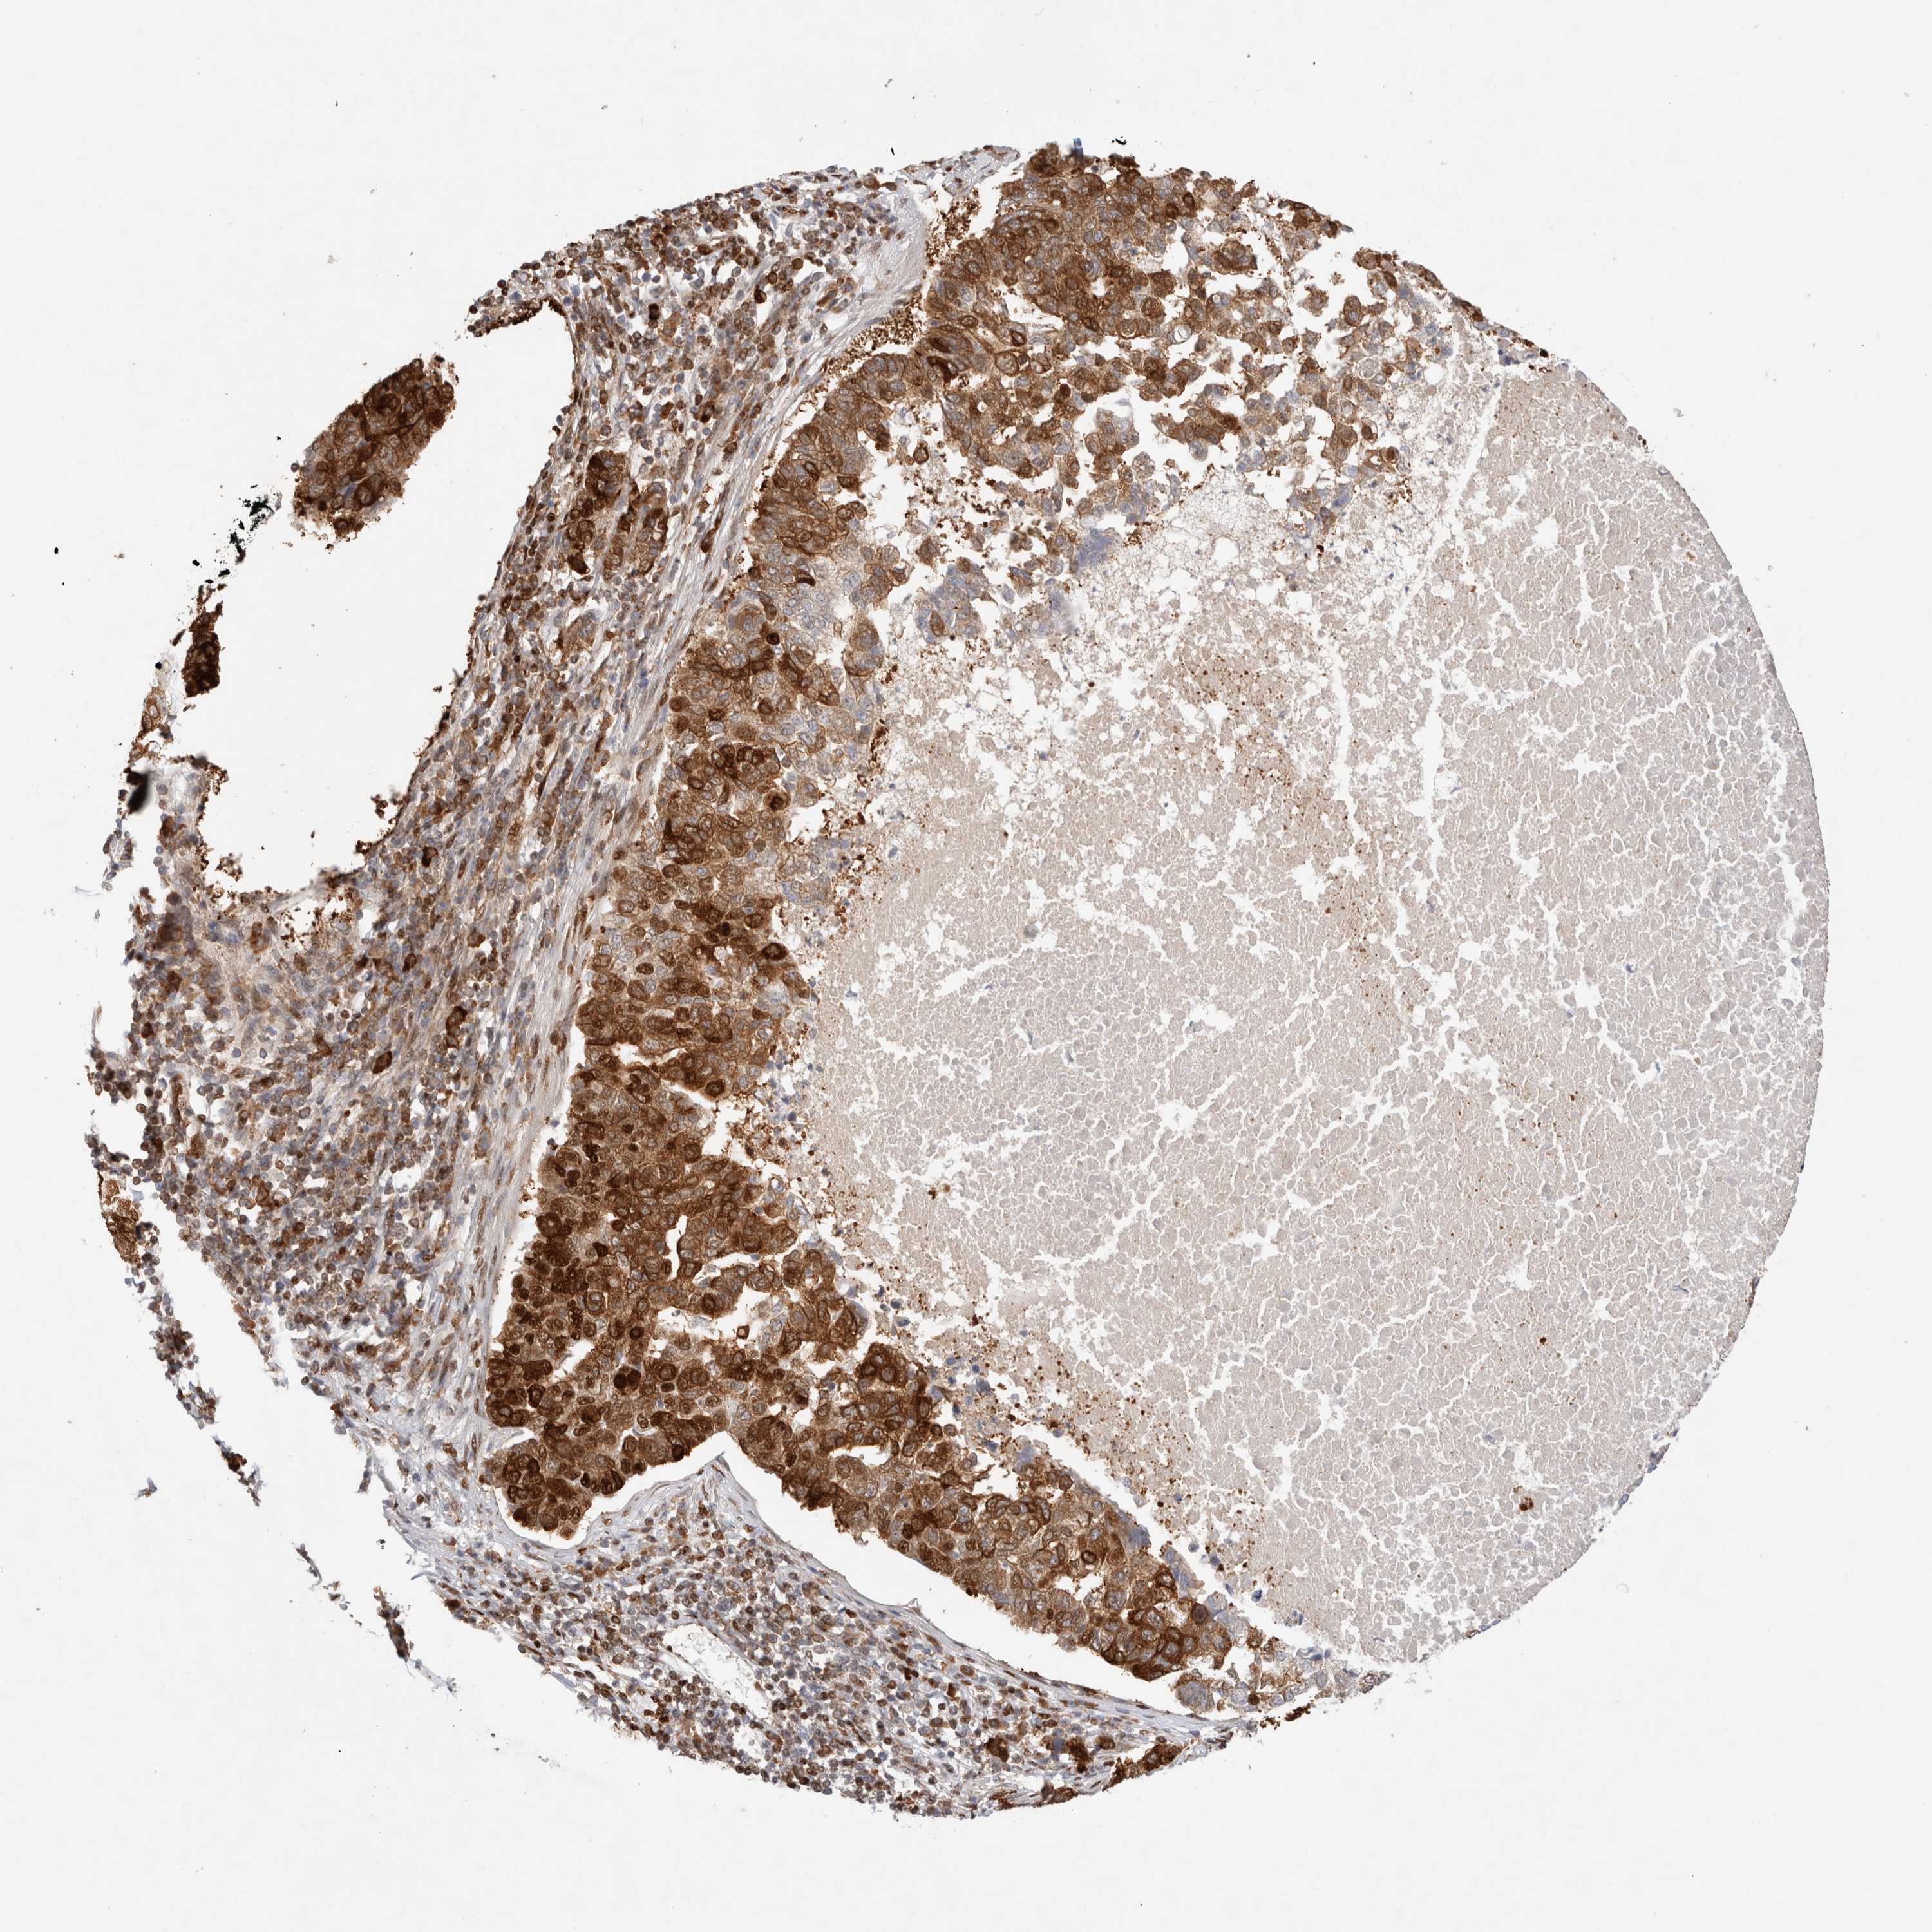

PANCREATIC CANCER - Protein expressioni

A mouse-over function shows sample information and annotation data. Click on an image to view it in a full screen mode. Samples can be filtered based on level of antibody staining by selecting one or several of the following categories: high, medium, low and not detected. The assay and annotation is described here.

Note that samples used for immunohistochemistry by the Human Protein Atlas do not correspond to samples in the TCGA dataset.

Antibody stainingi

Antibody staining in the annotated cell types in the current human tissue is reported as not detected, low, medium, or high, based on conventional immunohistochemistry profiling in selected tissues. This score is based on the combination of the staining intensity and fraction of stained cells.

Each image is clickable and will lead to virtual microscopy that enables deeper exploration of all samples and also displays staining intensity scores, fraction scores and subcellular localization as well as patient and tissue information for each sample.

Antibody HPA025958

Antibody CAB020722

Staining

High

Medium

Low

Not detected

Intensity

Strong

Moderate

Weak

Negative

Quantity

>75%

75%-25%

<25%

None

Location

Nuclear

Cytoplasmic/membranous

Cytoplasmic/membranous,nuclear

Adenocarcinoma, NOS

Adenocarcinoma, metastatic, NOS